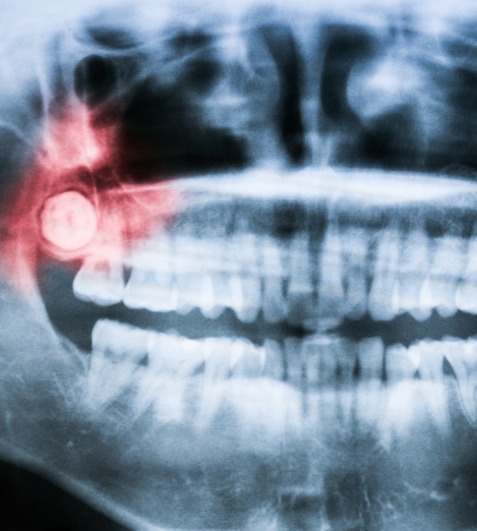

Wisdom Tooth Surgeries - Impaction

View →

Wisdom Tooth Surgery: We provide safe and precise surgical extraction of impacted or difficult wisdom teeth while minimizing discomfort and complications.